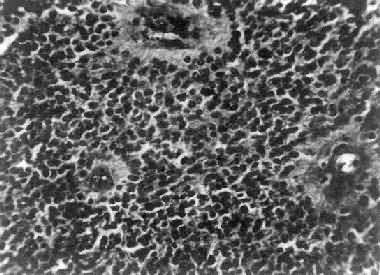

肉眼观,瘤组织呈鱼肉状,色灰红。镜下,肿瘤由圆形、椭圆形或胡萝卜形细胞构成,胞核着色深,胞浆少而边界不清楚,有多少不等的核分裂像。细胞密集,间质中有纤细的纤维,血管不多。瘤细胞环绕一个嗜银性纤细的神经纤维中心作放射状排列形成典型的菊形团(图16-26),这对髓母细胞瘤的病理诊断有一定的意义。瘤细胞具有向神经元及神经胶质双向分化的潜能,既能向神经母细胞、节神经细胞分化,也能向胶质母细胞、星形胶质细胞分化。如瘤细胞侵入软脑膜,可在蛛网膜下腔脑脊液中广泛播散转移。

图16-26 髓母细胞瘤

瘤细胞较小,着色深,密集排列,有菊形团形成